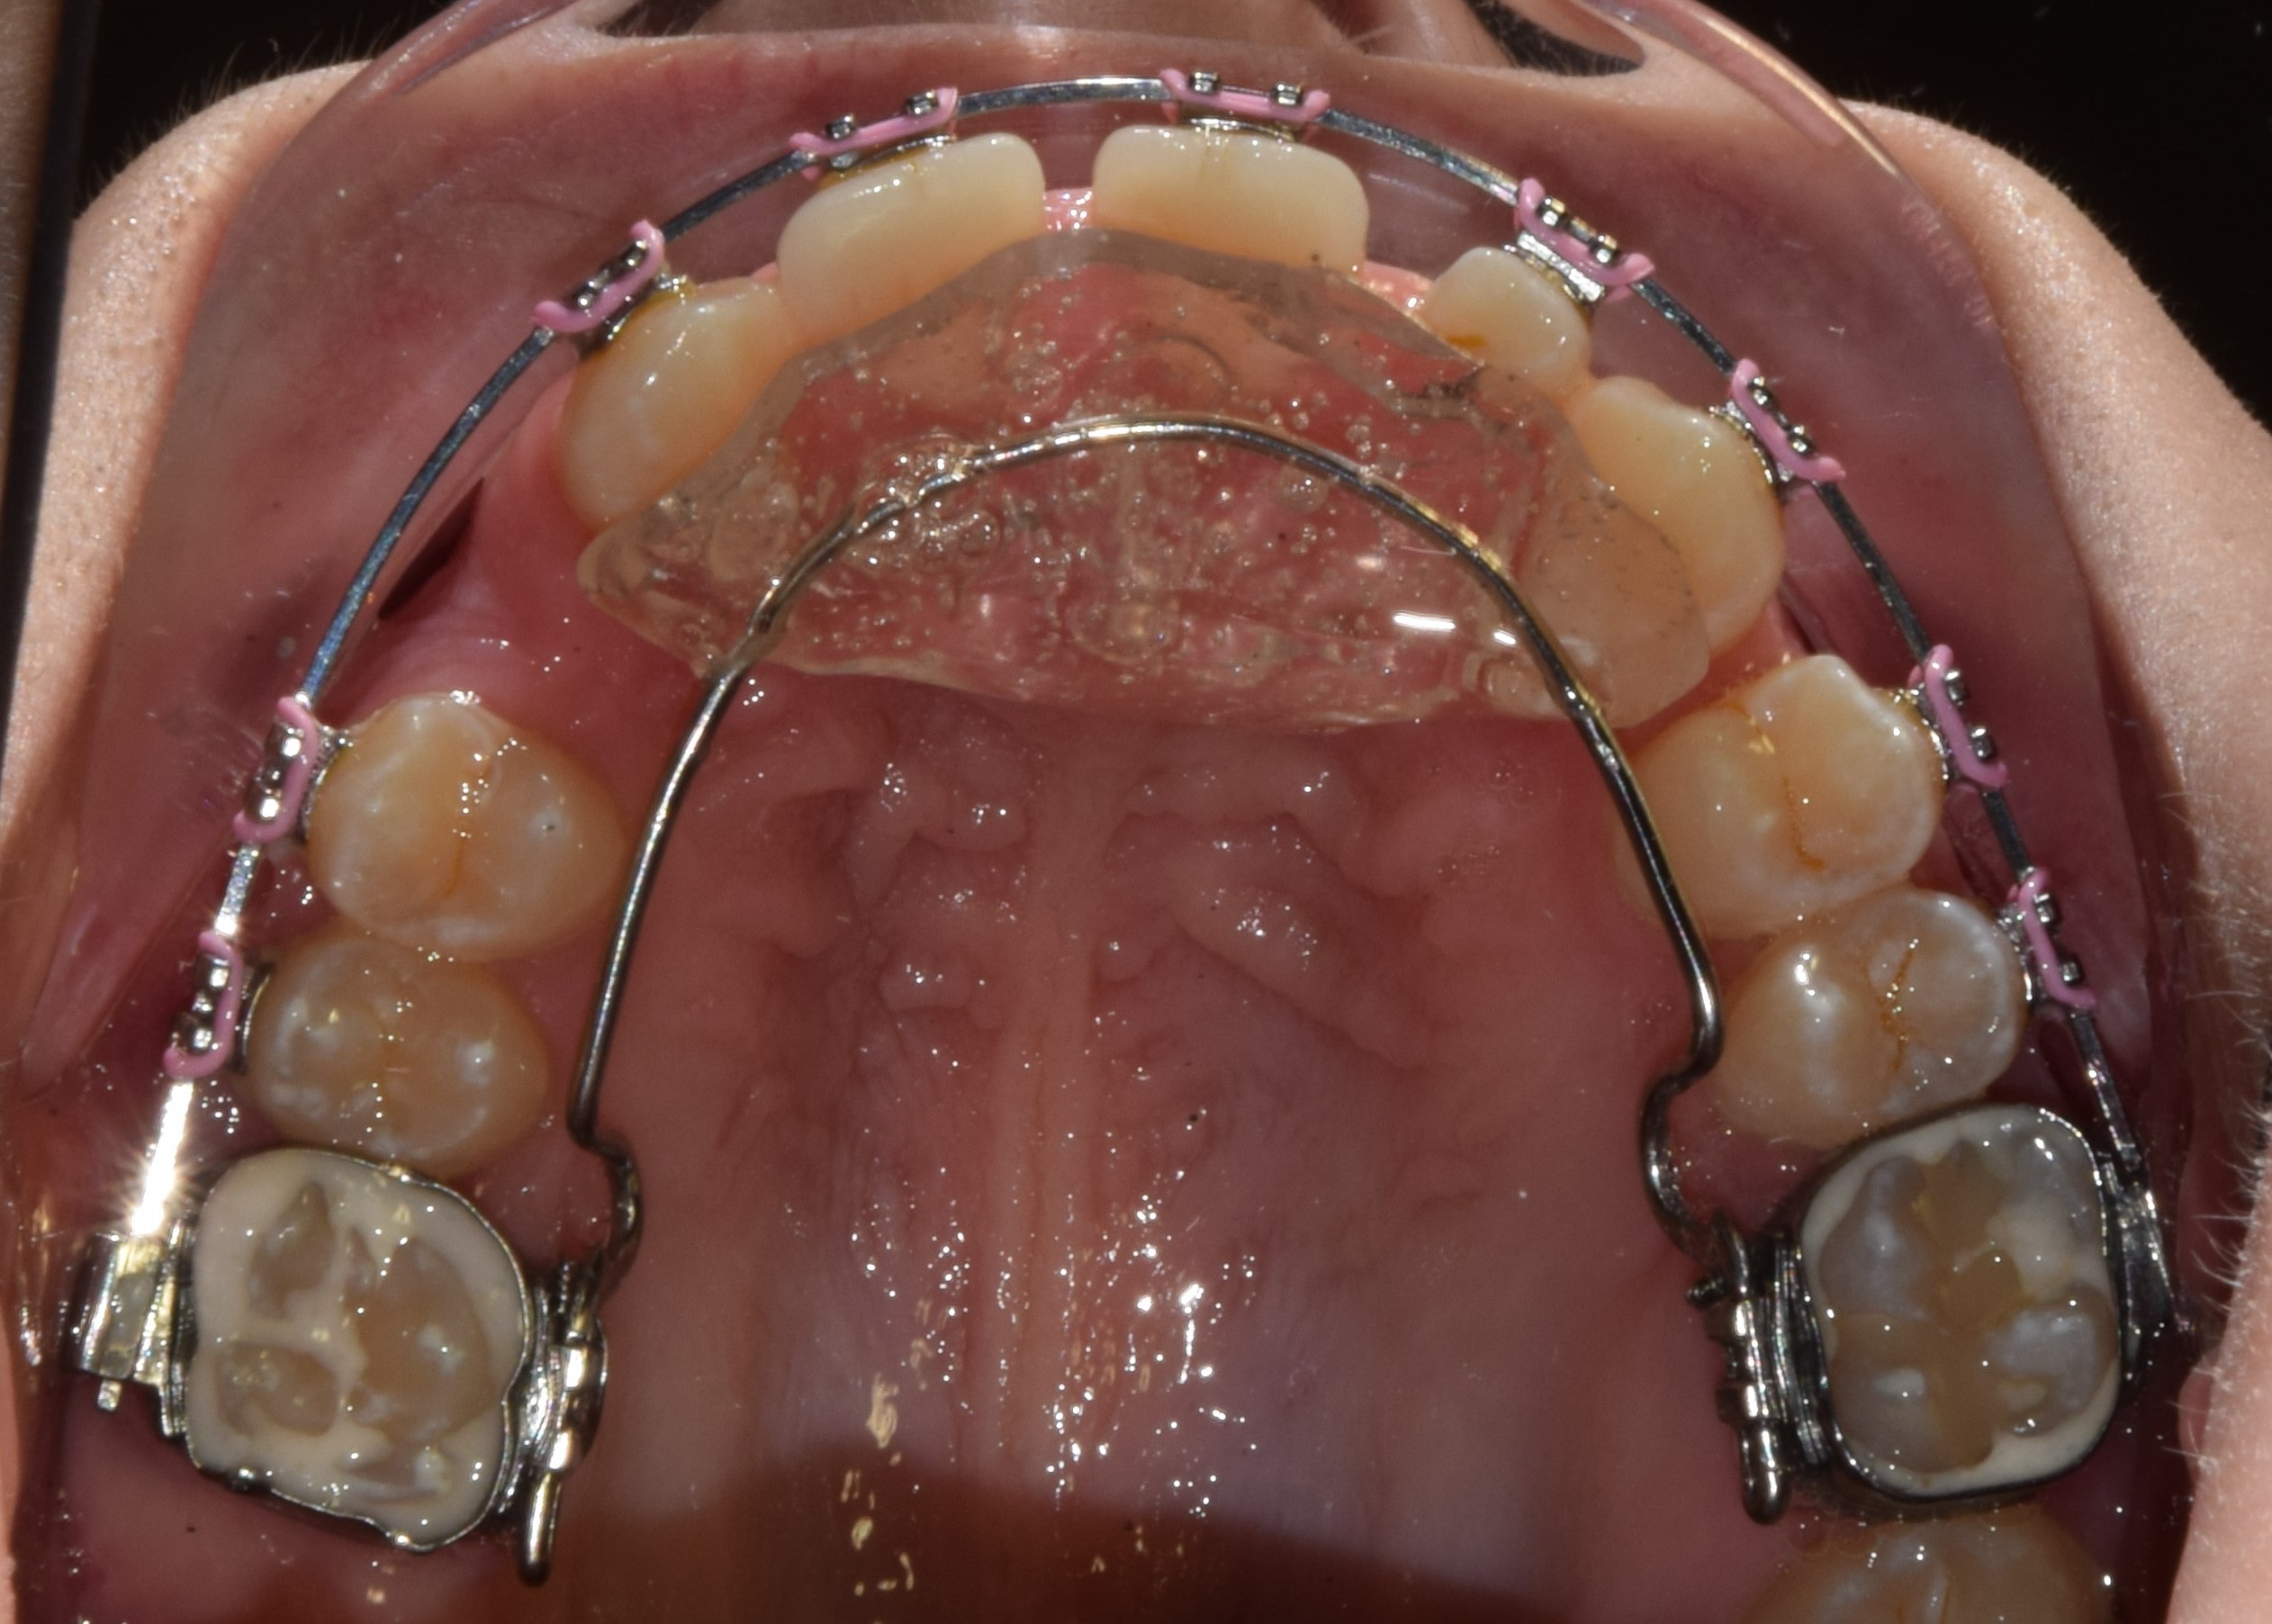

Hyrax

Fiatalkorban a felső állcsont tágítására alkalmas rögzített fogszabályozó készülék. Működése a felső állcsont közepén található csontvarrat (sutura palatina mediana) megnyitásán alapszik. Ilyenkor a két állcsontfelet távolítjuk egymástól. A hyrax maradófogazatban a felső első kisőrlőkön és első nagyőrlőkön rögzül, vegyesfogazatban pedig az első maradó nagyőrlőn és a tejőrlőkön (esetleg tej szemfogon). A vegyesfogazati hyrax készülhet fémből, vagy akrilátból (ez a splint hyrax). A hyrax közepén, a szájpad mélyére süllyesztve található egy csavar, amelyet a pácienseknek, szülőknek otthon kell tekerni. Fiatalkorban (7-9 év) ez 3 naponta 1 tekerést jelent, míg később (9-12 év) naponta 2 tekerést. A készülék működése során a felső állcsont tágul, a mosoly szélesedik, a torlódások spontán oldódnak, és a felső metszőfogak között rés keletkezik (ez idővel magától zárul). A felső állcsont tágulásával az alsó állcsont gyakran spontán előrehelyeződik (megoldva ezzel pl. egy disztálharapást). Átjárhatóbbá válnak a légutak, javul a szervezet és az agy oxigenizációja, ezzel a gyerkőcök alvása, kipihentsége, koncentrációja. Általam sokat használt és kedvelt készülék a hyrax. Fontos megjegyeznem, hogy a fent leírt, ijesztően hangzó mozgatások a pácienseim beszámolói alapján semmilyen fájdalommal nem járnak, és bár drasztikusnak tűnhet a folyamat, a gyerekek által egyik legjobban tolerált készülék. Kezelés hossza: 7-12 hónap. Kontrollok gyakorisága: az első 2-3 hétben hetente, később 4-8 hetente. A kezelés befejeztével vagy Goshgarian kerül fel az eredmény megtartására, vagy teljes rögzített fogszabályzó ragasztásával folytatódik a terápia.